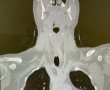

איזה נס: האב אכל את כריך הטונה של בנו בן ה-4 | זה נגמר בניתוח חירום

בתוך הכריך השתרבב ברזל חד שנתקע בגרונו של האב • "הייתה לנו כאן שרשרת ניסים"